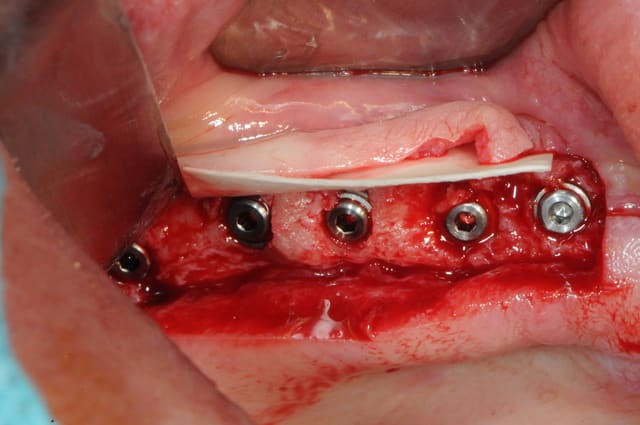

mais horreur! Oh, rage! oh désespoir! deux implants se mettent à tourner quand on applique le couple de serrage préconisé pour les piliers coniques.

intervention le surlendemain pour dépose et repose (si possible)

et là! ...c'est le drame!

keske je découvre?!!

non pas 2 mais 4 implants en difficultés (très peu mobiles, mais quand même), et puis surtout une grosse fonte osseuse sur plusieurs spires. la fonte prend la forme d'une cuvette.

jamais eu ça auparavant ! d'autant plus qu'il n'y a pas de saignement au sondage et pas de suppuration.

donc dépose, curetage, pose d'implants de diamètre plus importants ,mise en place Bio-Os et membrane Bio Gide